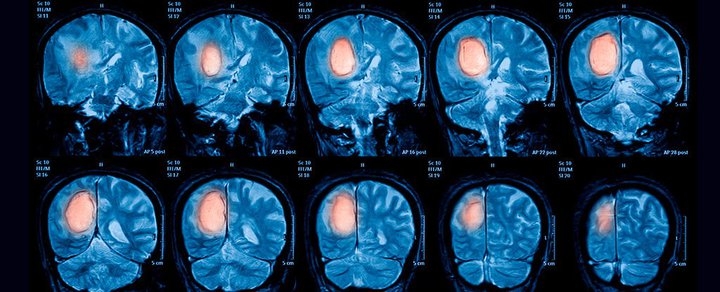

Новое исследование ученых не показало связи между контактом с высокочастотным электромагнитным полем и риском развития глиомы или менингиомы — опухолей мозга. Отмечается, что нынешнее исследование — самое крупное из тех, которые касались этой темы.

В нем участвовали четыре тысячи пациентов с глиомами и менингиомами, а также более пяти тысяч человек из контрольной группы из семи стран. Среди участников наблюдения были люди, постоянно работающие вблизи источников электромагнитного поля вроде радаров, телекоммуникационного и медицинского оборудования.

При этом исследователи отметили, что хоть и не обнаружили прямой связи между излучением и риском появления опухолей, но наблюдали у некоторых пациентов признаки повышенного риска в верхней группе высокочастотного излучения. Это говорит о том, что исследование необходимо продолжить.